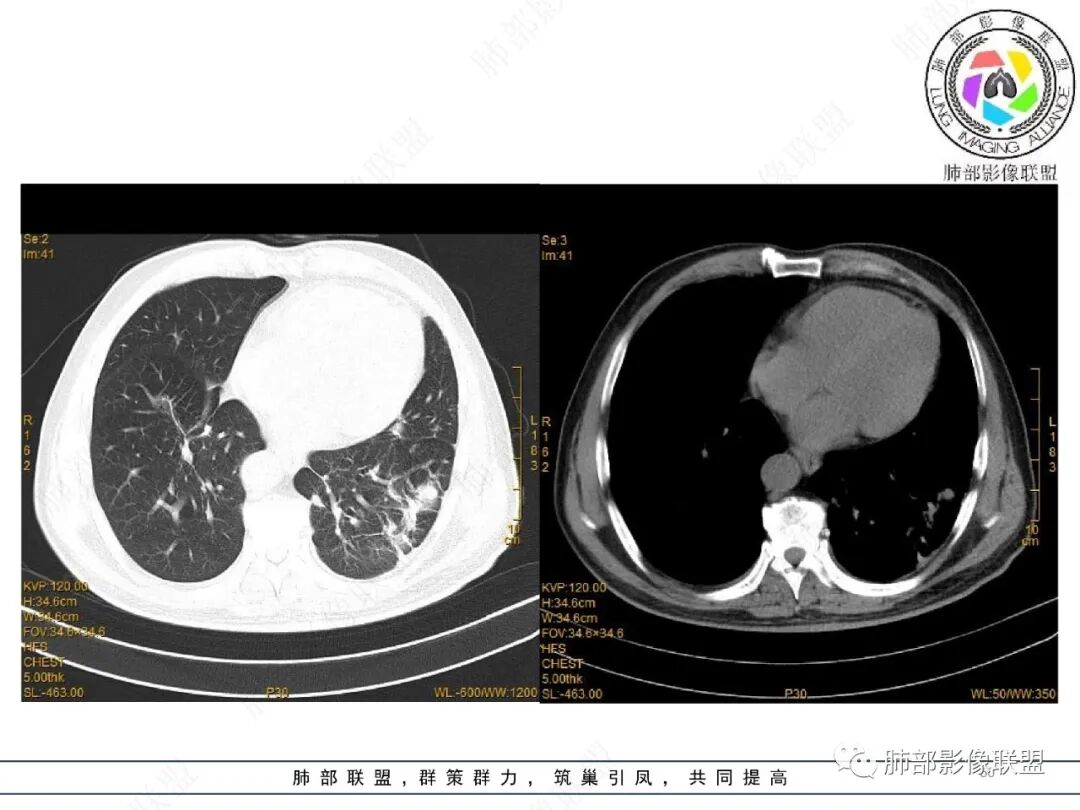

2022.2.17CT显示两肺中内带多发结节影、斑片影、条索影,部分病灶侧向融合与胸膜平行。部分病灶沿着支气管血管束分布、其内支气管稍扩张。部分病灶呈反晕征。大部分病灶边界显示清晰,部分病灶周围可见边界不清的GGO。2022.4.12CT显示两肺中内带多发结节影、条索状、条带状高密度影,边界收缩平直凹陷,大部分病灶沿着支气管血管束分布,亦有位于胸膜下侧向融合与胸膜平行的病灶。总体与第一次CT对比两肺病灶明显吸收。